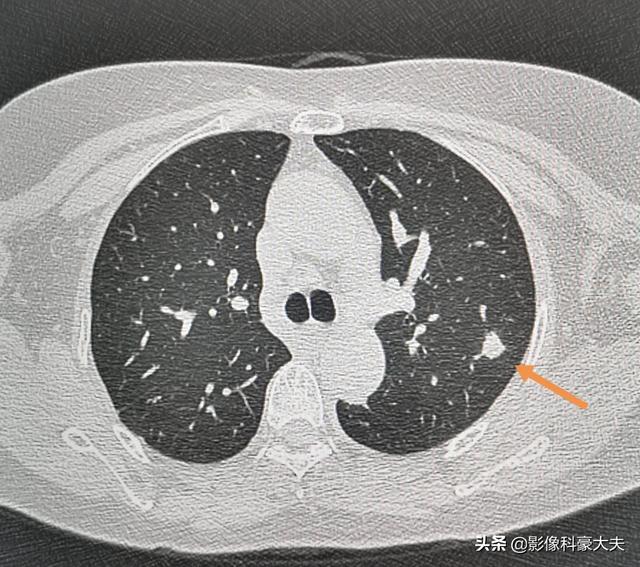

Il s'agit d'un patient âgé, l'examen physique a révélé des nodules pulmonaires, deux mois plus tard l'examen a absorbé, n'a pas utilisé de traitement, juste une attention au repos et à l'exercice approprié, considéré comme une infection de faible virulence.